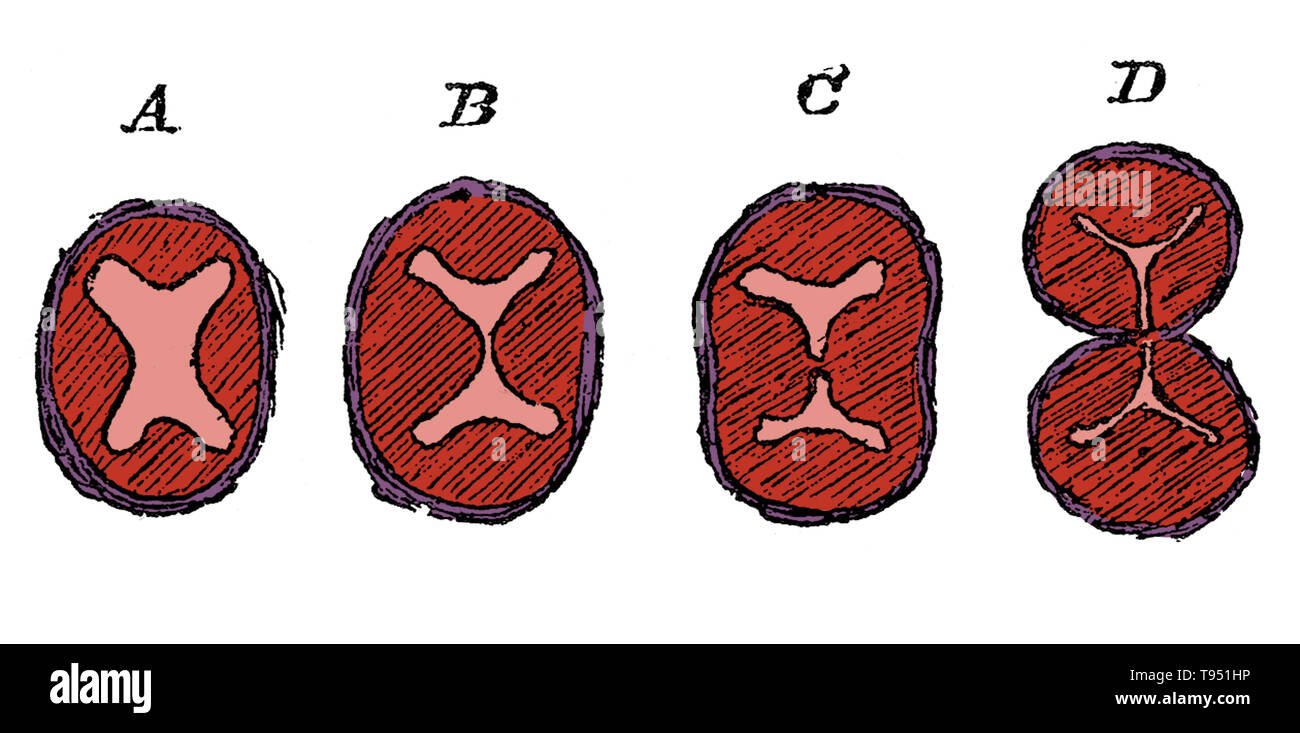

Diagram showing the division of the lower part of the bulbus aorta, aorta, and the formation of the semilunar valves. A, undivided truncus arteriosus with four endocardial cushions; B, advance of the two lateral cushions resulting in the division of the lumen; C, projection of three endocardial cushions in each part; D, the separation into aorta and pulmonary trunks completed. Stock Photohttps://www.alamy.com/image-license-details/?v=1https://www.alamy.com/diagram-showing-the-division-of-the-lower-part-of-the-bulbus-aorta-aorta-and-the-formation-of-the-semilunar-valves-a-undivided-truncus-arteriosus-with-four-endocardial-cushions-b-advance-of-the-two-lateral-cushions-resulting-in-the-division-of-the-lumen-c-projection-of-three-endocardial-cushions-in-each-part-d-the-separation-into-aorta-and-pulmonary-trunks-completed-image246588098.html

Diagram showing the division of the lower part of the bulbus aorta, aorta, and the formation of the semilunar valves. A, undivided truncus arteriosus with four endocardial cushions; B, advance of the two lateral cushions resulting in the division of the lumen; C, projection of three endocardial cushions in each part; D, the separation into aorta and pulmonary trunks completed. Stock Photohttps://www.alamy.com/image-license-details/?v=1https://www.alamy.com/diagram-showing-the-division-of-the-lower-part-of-the-bulbus-aorta-aorta-and-the-formation-of-the-semilunar-valves-a-undivided-truncus-arteriosus-with-four-endocardial-cushions-b-advance-of-the-two-lateral-cushions-resulting-in-the-division-of-the-lumen-c-projection-of-three-endocardial-cushions-in-each-part-d-the-separation-into-aorta-and-pulmonary-trunks-completed-image246588098.htmlRMT951HP–Diagram showing the division of the lower part of the bulbus aorta, aorta, and the formation of the semilunar valves. A, undivided truncus arteriosus with four endocardial cushions; B, advance of the two lateral cushions resulting in the division of the lumen; C, projection of three endocardial cushions in each part; D, the separation into aorta and pulmonary trunks completed.